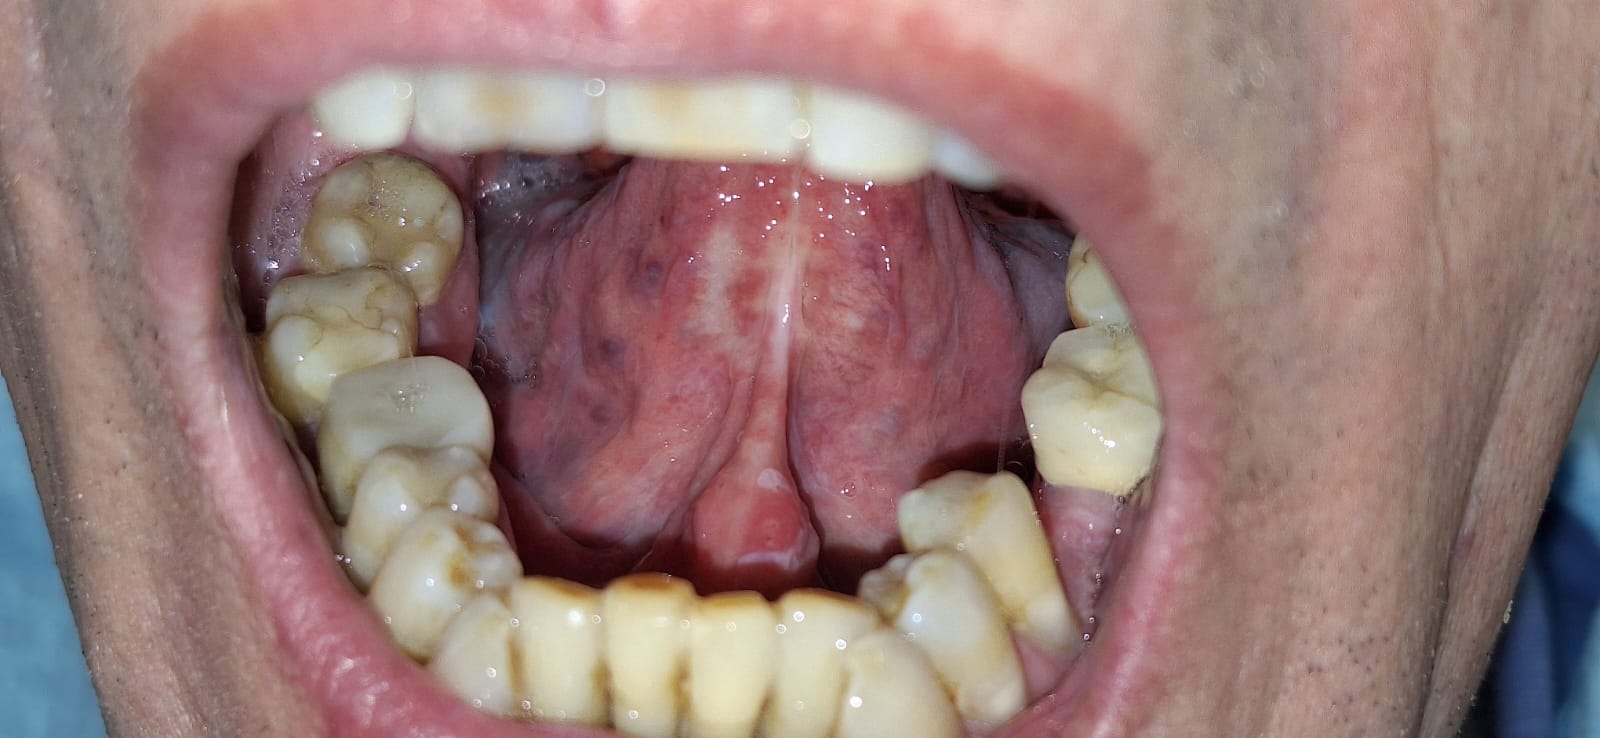

Leukoplakia to jedna z najczęstszych zmian przednowotworowych w obrębie jamy ustnej (o zwiększonym ryzyku wystąpienia nowotworu złośliwego). Charakteryzuje się obecnością białych/szarych plam lub smug na powierzchni błony śluzowej.

Poniżej prezentujemy leczenie i usunięcie leukoplakii, hyperkeratozy dna jamy ustnej i brzusznej części języka laserem CO2.

Po leczeniu